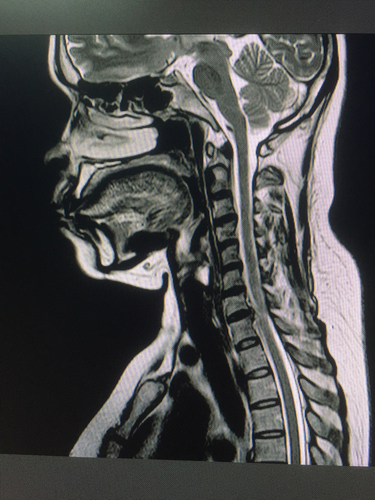

2. Imaging Studies: An MRI scan must show intervertebral disc bulging or herniation, as well as spinal stenosis that compresses the nerve root.

A spine specialist at DRHC will review your medical history, symptoms, and imaging (MRI/CT scans) to determine if FED is the best option for your condition.